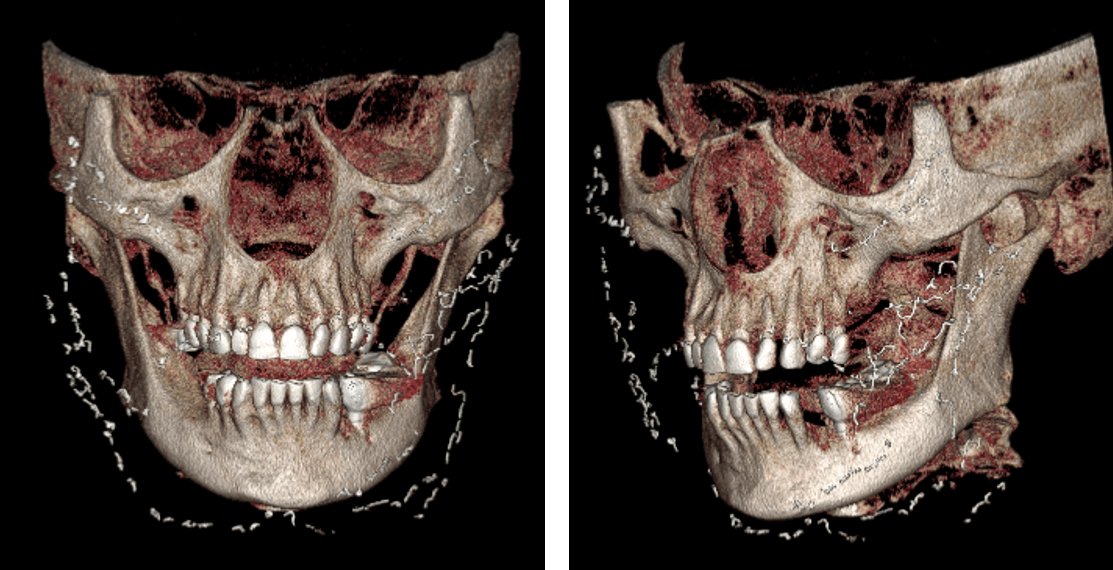

Fig.4

En la representación tridimensional (Fig.4) se observan de mejor manera las imágenes hiperdensas anteriormente descritas. Estas se observan de forma aparentemente alargada. Se consideran signos tomográficos de una secuela quirúrgica relacionado con la cirugía estética. Las imágenes hiperdensas son compatibles con hilos de filamento de oro u otro material metálico.